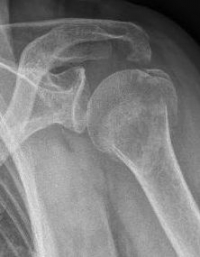

Proximaler Oberarmbruch3Proximaler Oberarmbruch4

Picture: The subcapital humeral fracture shown here in the axis is not broken and only slightly bruised, so that a conservative therapy is possible. The left image shows the follow-up after 3 weeks. The patient has already started physiotherapy. The x-ray shows an increase bone healing.